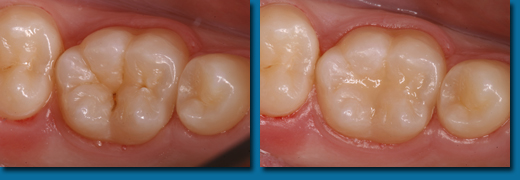

歯並びが悪くなってから治療することを歯列矯正といいますが、乳歯の頃から出てくる歯並びが悪くなる兆候を早期に発見しそれを改善しながらきれいな歯並びの永久歯にしていくことを咬合育成といいます。専門的には歯列矯正と咬合育成は別の物と区別されています。咬合育成は歯並びの予防と考えられ当医院では積極的に取り組み、多くの歯並びの良い子供が育っています。写真の左は乳歯の時、右が永久歯になった時のものです。